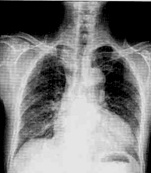

病史:男性,65岁,活动后胸闷6个月。既往高血压病史15年。诊断:

○ 靴型心

○ 梨形心

○ 普大型心脏

○ 正常心脏

○ 以上均不是